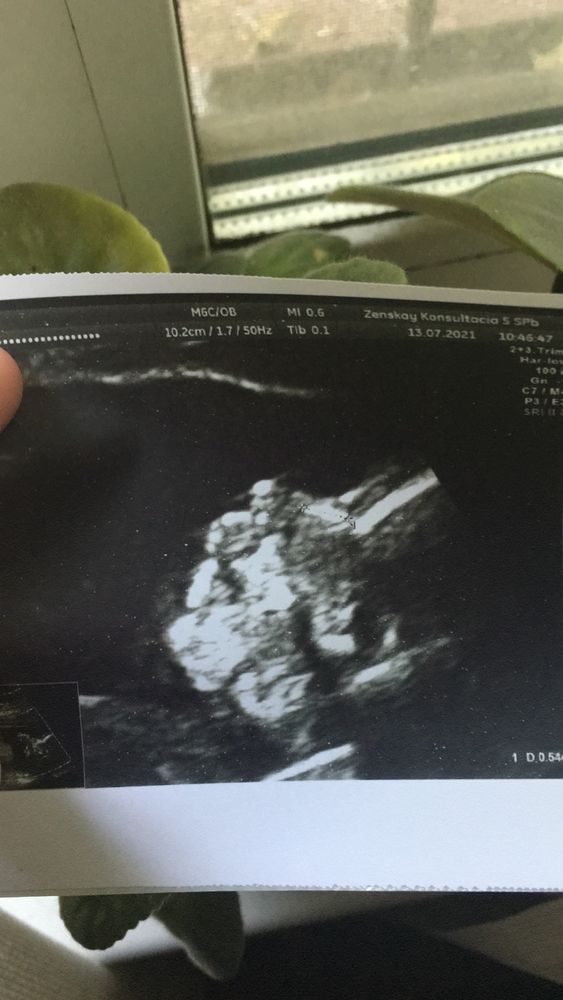

Вчера была на втором скрининге, с малышкой все прекрасно, развивается по сроку, растёт и пьёт воды.

Врач назвала ее красавицей)